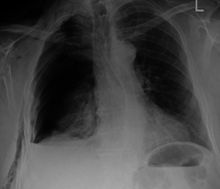

| An X ray showing multiple old fractured ribs of the person's left side as marked by the oval. | |

A rib fracture is a break or fracture in one or more of the bones making up the rib cage.[1] Fractures of the first and second ribs may be more likely to be associated with head and facial injuries than other rib fractures.[2] The middle ribs are the ones most commonly fractured.[3] Fractures usually occur from direct blows or from indirect crushing injuries. A rib fracture has the complication of potentially causing a pulmonary contusion.[4] Rib fractures are usually quite painful because the ribs have to move to allow for breathing. When several ribs are broken in several places a flail chest results, and the detached bone sections will move separately from the rest of the chest.[5]